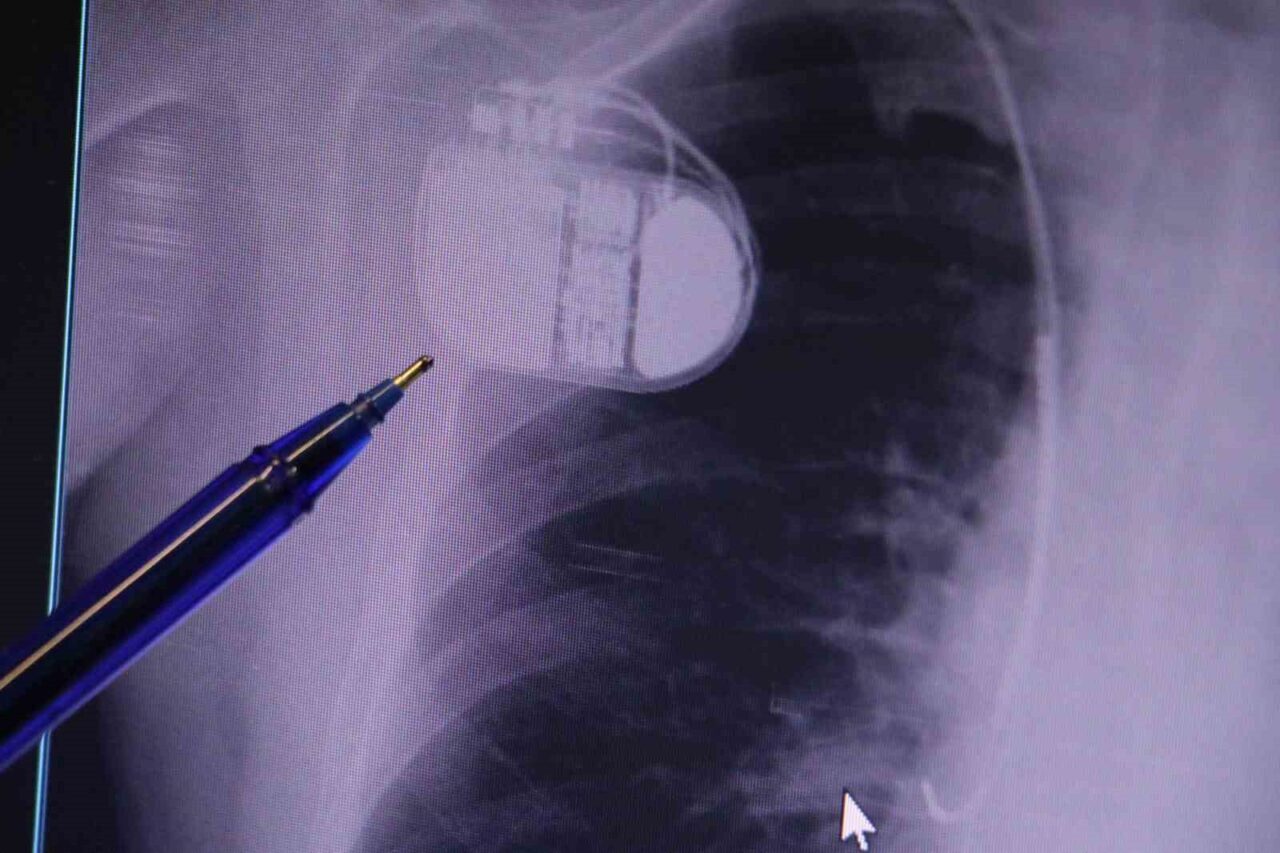

Dr. İsmail Erdoğu, kalp pillerinin önemine dikkat çekerek, yeni nesil kalp pillerinin MR cihazları ile uyumlu çalıştığını, ancak yine de tarama cihazlarından geçilmesinin önerilmediğini belirtti. Soğuk nedeniyle vücutta oluşan titremelerin, kalp pilinin yanılmasına yol açabileceğini ve bu durumun istenmeyen şoklamalara neden olabileceğini ifade etti. “Bu nedenle hastalarımızın soğuk havalarda daha fazla dikkat göstermelerini bekliyoruz” dedi.

Kalp pillerinin MR cihazlarında kullanılabildiğini hatırlatan Dr. Erdoğu, bu durumun önemli bir cerrahi önemi bulunduğunu ve kalp pilinin, tıp alanındaki son 30 yılın en büyük yeniliklerinden biri olduğunu dile getirdi. Kalp pilleri, hastaların yaşama mücadelesinde önemli bir rol oynamakta. “Bir defibrilatör olmadan hastanın ritmini düzeltmek mümkün değil. Kalp pili, hastanın durumunu algılayarak gereksinim duyulduğunda devreye giriyor ve hastayı hayata döndürebiliyor. Ancak soğuk hava, kalp pilinin hafızasında karışıklığa neden olabilir. Bu durumu önlemek için, kalp pili bulunan kişilerin kış aylarında ekstra dikkatli olmalarını öneriyoruz” diye açıkladı.